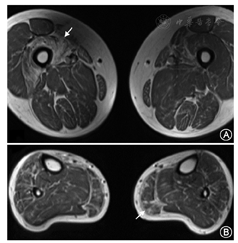

主要包括头颅及肌肉的MRI。DM患者的肌肉MRI的最主要表现为肌肉脂肪化及肌萎缩,以下肢远端肌群受累为主。受累程度与患者临床症状相平行(图3)。在DM1型患者的头颅MRI中,可见有弥漫性脑白质病变,部分患者可出现脑萎缩。而在DM2型患者中,头颅MRI多表现正常。

Magnetic resonance imaging of one myotonic dystrophy patient. A: Increased intramuscular T1 image signaling within the bilateral thigh muscles; B:T1-weighted hyperintense area in the musculi soleus